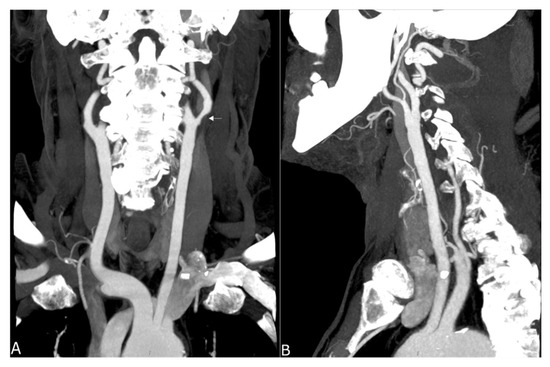

Figure 4.

Maximum intensity projection of a supra-aortic UHR-CTA, (A) coronal projection showing an internal carotid artery plaque (white arrow) as well as contrast and delineation of, e.g., the thyrocervical trunk; (B) sagittal projection.

In summary, the subjective analysis of all images showed excellent results for the applied qualitative parameters such as overall image quality, overall contrast noise and artefacts, the latter focusing on streaks within the posterior fossa. A high-rated vessel contrast and delineation could also be observed, which were not only limited to the large cerebral vessels but also appeared in the smaller vessel sections, especially in the deep cerebral perforators (e.g., lenticulostriate arteries). Patient examples are given in Figure 2, Figure 3, Figure 4 and Figure 5. Interrater reliability was ascertained by applying Cohen’s kappa coefficient and showed a fair agreement (k = 0.26).

Studies on coronary artery and small visceral artery CTAs [11,12] have recently shown that the UHR-CT system is highly suitable for a significant improvement in image quality, SNR, CNR and an enhanced vascular imaging. Our investigation, which to our best knowledge represents the first study to evaluate image quality, contrast and delineation of the supra-aortic vessels and the small perforating arteries, confirms the excellent qualification of the UHR-CTA as a diagnostic tool in radiological and vascular imaging. Hence, the use of UHR-CTA will be of high value in various clinical settings, especially when a high resolution is inevitable for an accurate diagnosis and optimized patient care. In detail, advances in the diagnosis of aneurysms and steno-occlusive diseases may be reached, especially when looking at aneurysm configuration, and peculiarities or irregularities of the of aneurysm wall. UHR diagnostics may additionally improve pre-invasive planning of subsequent digital subtraction angiographies and interventions, enabling earlier and more individualized treatment decisions. An additional benefit will arise from a substantially reduced radiation exposure due to the omission or the time reduction in follow-up examinations.